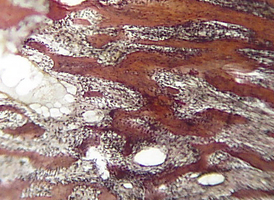

Морфологическое и лабора-торное обоснование приме-нения комбинированных трансплантатов при костной пластике челюстей

Экспериментальное исследование. Изучение морфогенеза после заме-щения дефектов нижней челюсти смесью лиофилизированной алло-спонгиозы и “аллогенного гидроксиапатита” в соотношении 1:1 и 3:1.

Экспериментальное исследование. Изучение морфогенеза после заме-щения дефектов нижней челюсти смесью лиофилизированной алло-спонгиозы и “аллогенного гидроксиапатита” в соотношении 1:1 и 3:1.